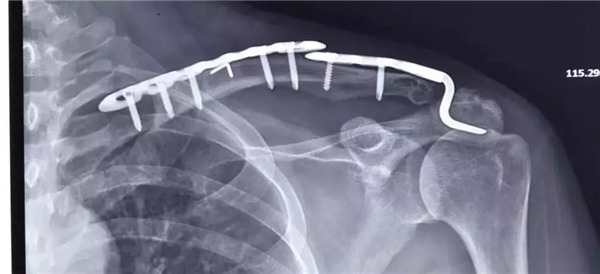

經(jīng)患者與家屬同意后,羅軍主任手術(shù)團(tuán)隊(duì)成功為患者實(shí)施了左肩鎖關(guān)節(jié)復(fù)位Y型Endobutton固定系統(tǒng)固定術(shù)。手術(shù)只用50分鐘時(shí)間。術(shù)后X片復(fù)查顯示肩鎖關(guān)節(jié)脫位完全復(fù)位,術(shù)后第二天楊女士在康復(fù)醫(yī)師指導(dǎo)下開始進(jìn)行左肩關(guān)節(jié)功能鍛煉,楊女士左肩部疼痛明顯減輕,左肩關(guān)節(jié)可抬起、前舉,功能較術(shù)前明顯改善,楊女士大約再經(jīng)過3-4周康復(fù)訓(xùn)練左肩關(guān)節(jié)功能可恢復(fù)正常。

術(shù)后拍片